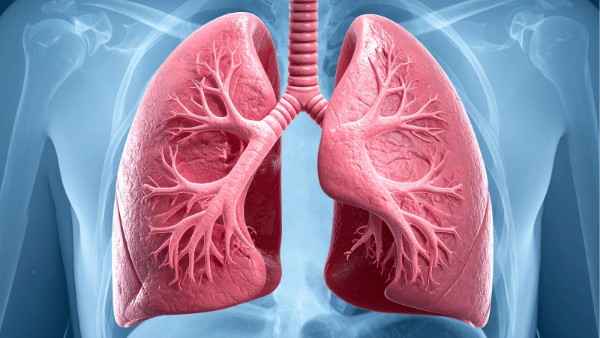

Understanding Respiratory & Allergic Conditions

Respiratory and allergic conditions refer to a group of disorders that affect the respiratory system and are often triggered by an over-reactive immune response to common substances. These conditions are characterized by inflammation of the airways, leading to difficulty in breathing and other related symptoms. They are chronic in nature and can significantly impact a person’s quality of life. The immune system, in these cases, mistakenly identifies harmless substances like pollen, dust, or certain foods as threats, releasing chemicals that cause allergic reactions.